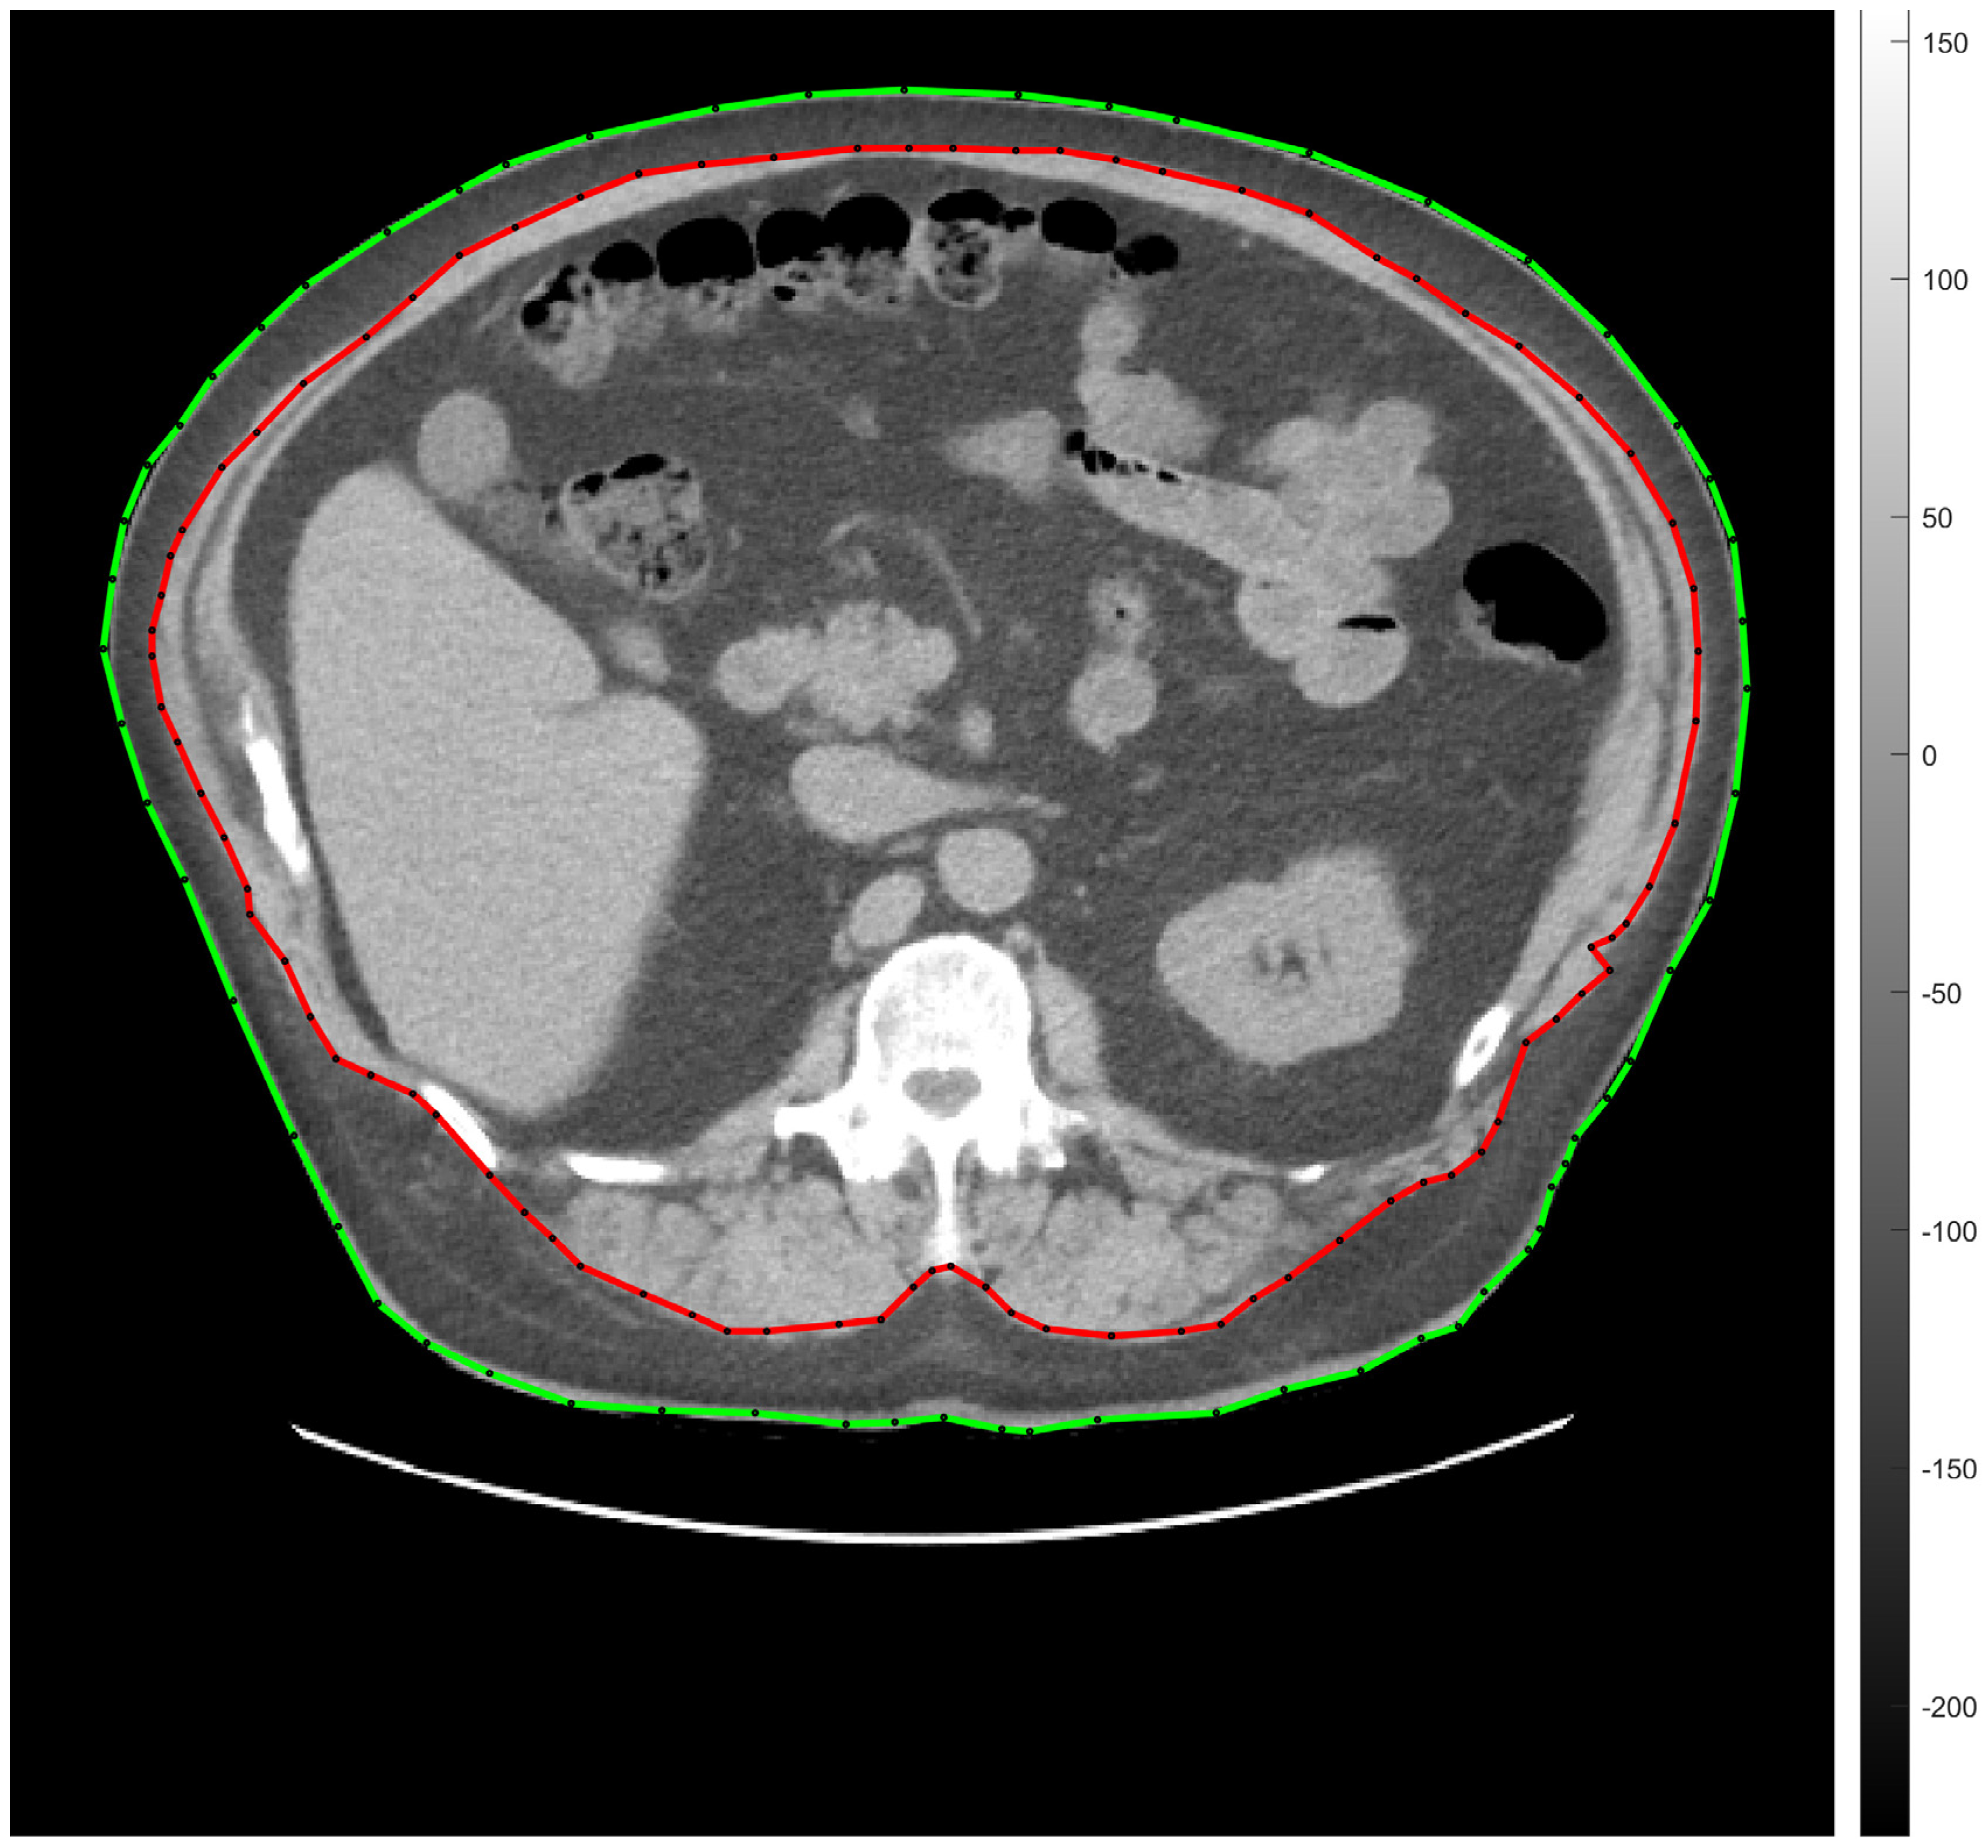

To quantify the ratio of visceral (VAT) and subcutaneous (SAT) abdominal fat tissue, transaxial low-dose CT images were performed using the CT compartment of the AnyScan positron emission tomography/computed tomography (PET/CT; Mediso Ltd., Budapest, Hungary) hybrid device with the following CT parameters: 120 kW and 100 mAs.

Abdominal fat segmentation was carried out by a semi-automatic method. Briefly, a transaxial CT slice—acquired at the level of vertebra L1—was chosen for image processing []. Thereafter, ROIs (regions of interest) representing the body contour (green line) and the abdominal cavity (red line) were manually deposited on the selected CT scans (seen on representative Figure 2).

Figure 2. Transaxial low-dose CT slice acquired at the level of vertebra L1 for the representation of semi-automatic abdominal fat tissue segmentation. The green line indicates the body contour, the red one is for the abdominal cavity. SAT and VAT were calculated by counting the segmented pixels between the green and the red ROIs, and within the area of the red ROI, respectively. CT, computed tomography; L1, vertebra lumbar I; SAT, subcutaneous adipose tissue; ROI, region of interest; VAT, visceral adipose tissue.

Fat tissue segmentation was performed according to the −190 and −30 HU (Hounsfield unit) range of attenuation. The amount of SAT and VAT was determined on the basis of the number and the volume of the segmented pixels measured between the red and the green lines (SAT) and under the red line (VAT). Seven of the involved participants did not consent to low-dose CT imaging.